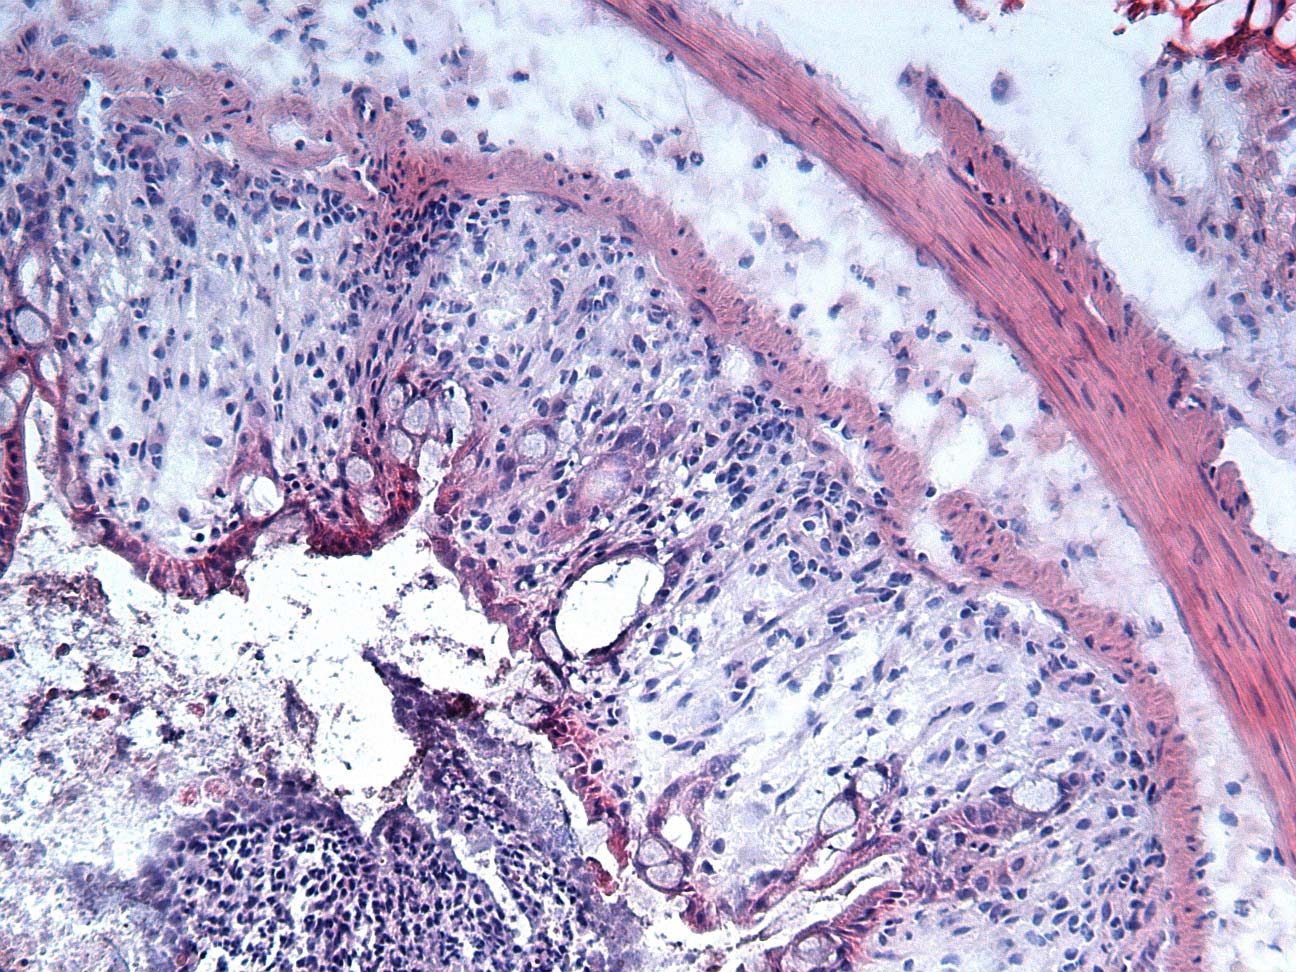

正常的老鼠腸組織

使用 DSS 誘導的腸組織使用 3% DSS 於飲用水中,作用 7 天。